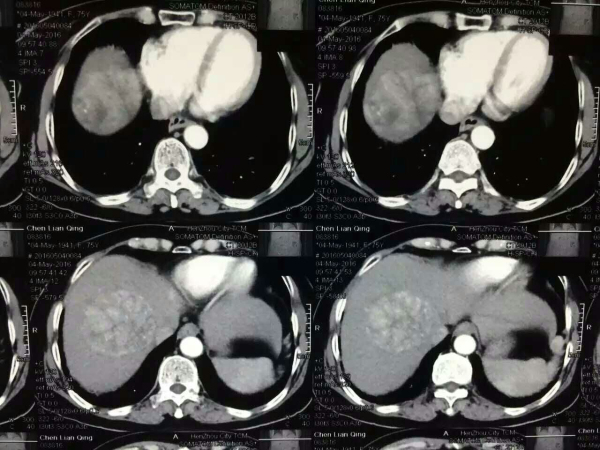

• 年龄不再是手术的绝对禁忌

年龄不再是手术的绝对禁忌

随着社会的进步、生活及医疗水平的提高,我国进入了老龄化社会,肝胆腺体外科也收治了越来越多的老龄患者。 陈阿姨今年76岁,大约1月前老人...

发布时间:2016-08-19 来源: